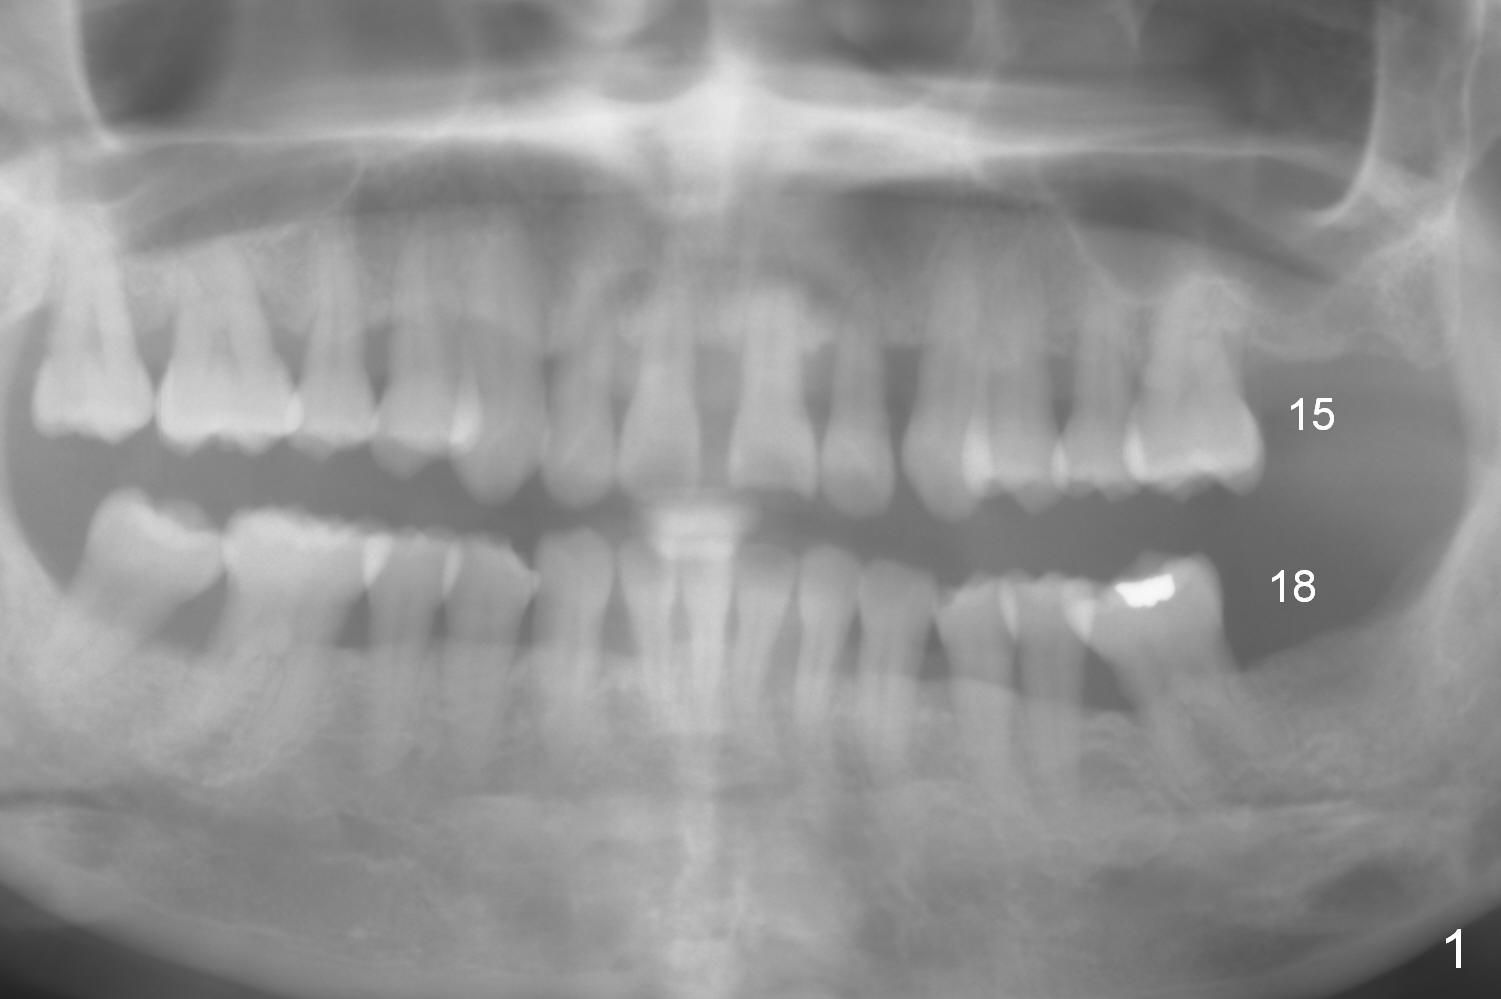

Implants Keep Posterior Vertical Height A 32-year-old woman is concerned about her upper anterior tooth flaring (Fig.1). She is eager for periodontal treatment. She masticates on the right side. The teeth #15 and 18 were extracted ~ 1 year ago. To lessen anterior flaring (take photos when she returns), implants are going to be placed at these sites (Fig.2,3). IBS and Magic Sinus Lift Kits will be used for #15. Magic Split gains access for 5 mm deep (gingival level), followed by ME 3 mm and next ME for 5 mm and Sinus lifter for 9 mm (bone level 7 mm, CMC). Or use the 4.3 mm drill from Magic Sinus Lift Kit for 5 mm, followed by Sinus Lifter for 9 mm. Insert PRF plugs into the sinus, followed by allograft (.5-1.0 mm) with Osteogen. If implant stability is low, place a healing abutment or screw. For #18 implant placement, palpate the ridge to determine the width. Trim the ridge if it is pointed. Also use Magic split for access and bone density testing. Either BEB or PBR will be adopted. The patient is interested in orthodontic treatment. Take Alginate impression and facial photos. Return to Upper Lower Molar Immediate Implant, IBS Xin Wei, DDS, PhD, MS 1st edition 11/15/2016, last revision 01/22/2017 |